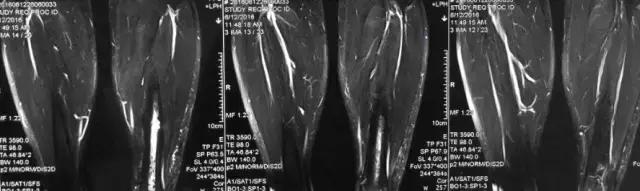

影像检查

核磁示中下段骨髓炎,上面切口处流脓,请问张主任你的意见要上手术吗?